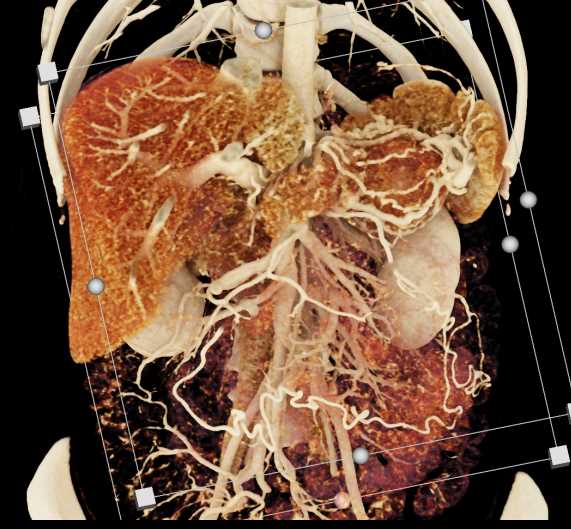

Neuroendocrine Tumor Pancreas